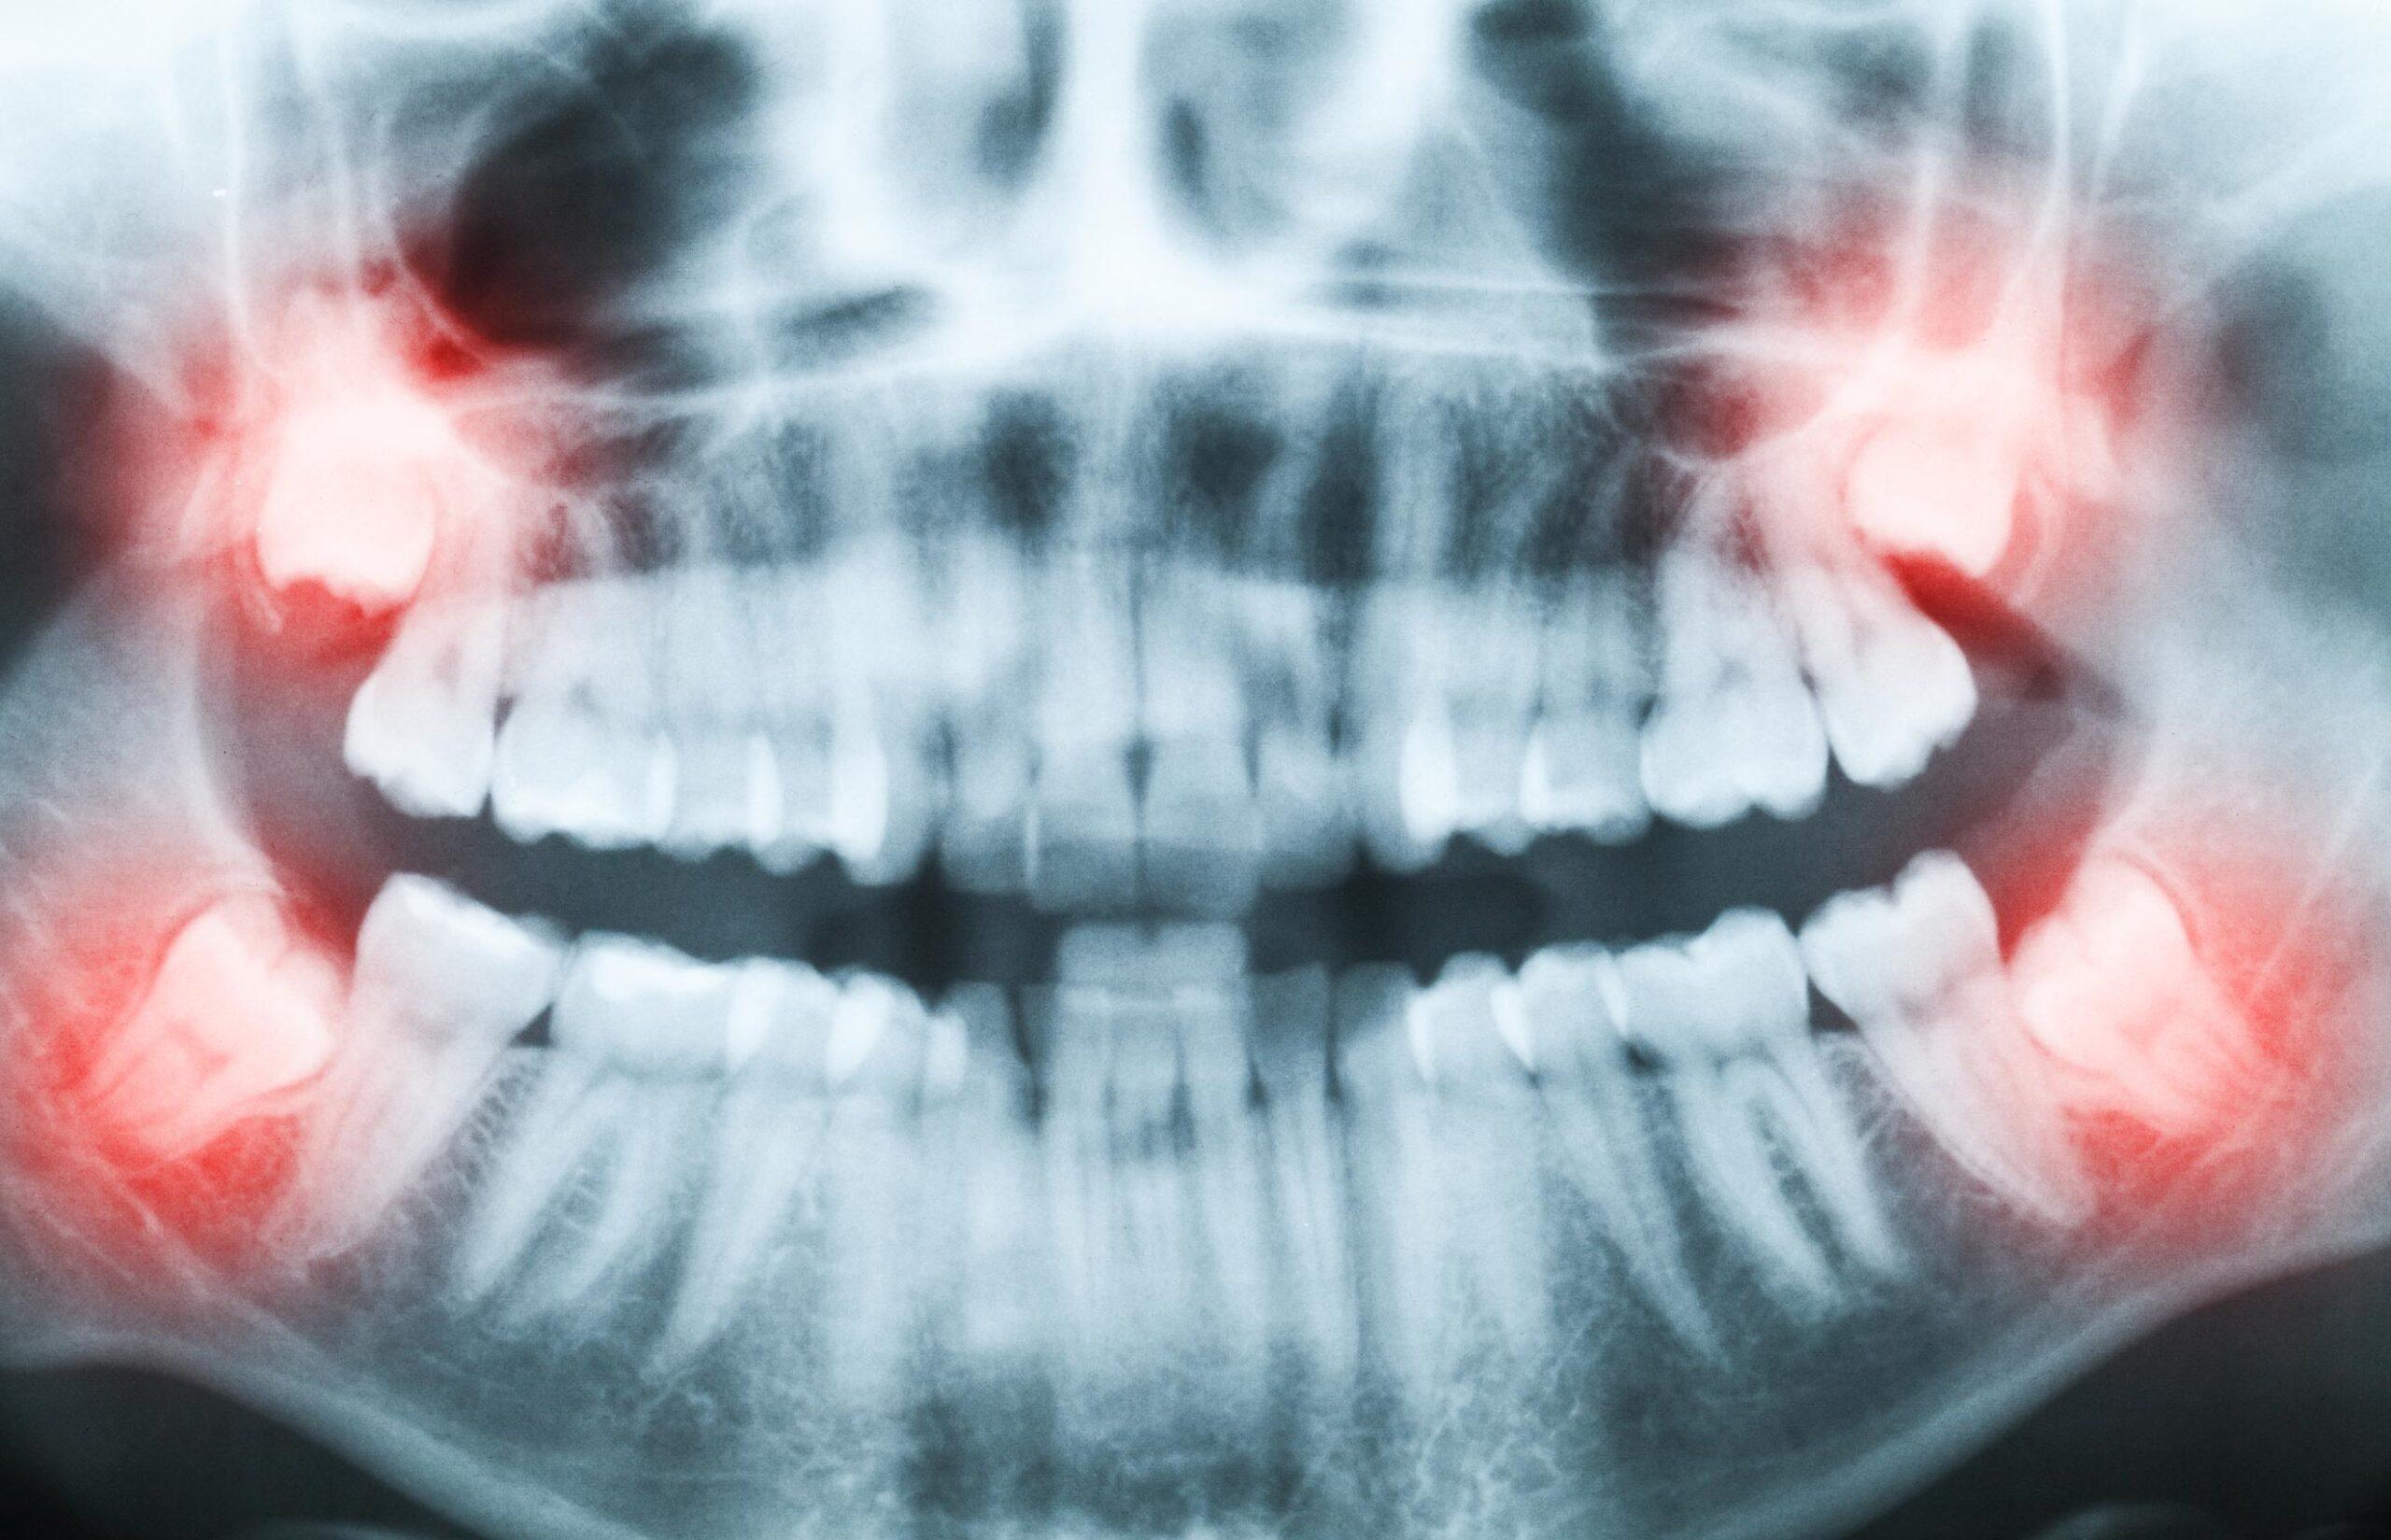

Wisdom teeth may require removal if they are:

• Partially erupted, which can allow bacteria to collect around the tooth and increase the risk of infection or gum inflammation

• Growing at an angle, placing pressure on neighbouring teeth or contributing to crowding

• Impacted beneath the gums or bone, which may lead to swelling, discomfort, or infection

• Associated with recurring pain, stiffness, or swelling in the jaw or surrounding gums